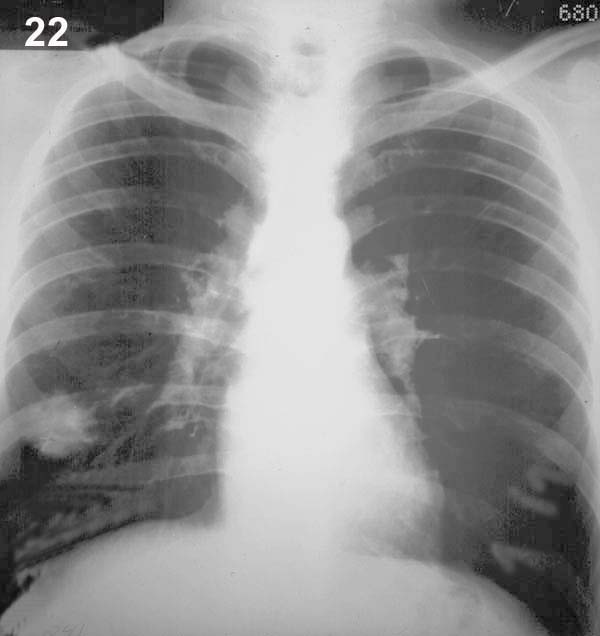

Comentario placa 22

En la base derecha se observa un nódulo redondeado de 30 mm de diámetro. Sus bordes presentan salientes agudas radiadas o espículas que son más frecuentes en procesos neoplásicos malignos.

Pase a la placa 23, examínela cuidadosamente y busque una anomalía que es difícil de ver.